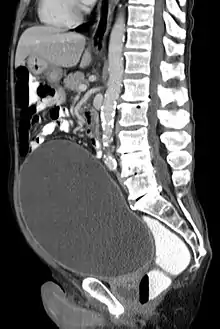

![]() أشعة مقطعية تظهر تضخم كبير في المثانة البولية بسبب احتباس البول. أشعة مقطعية تظهر تضخم كبير في المثانة البولية بسبب احتباس البول. | |